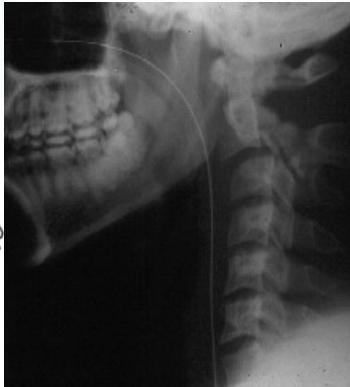

Lateral View

- All C- vertebrae & upper T1

- Prevertebral soft tissue width

- Four parallel curves

- Front of vertebral bodies

- Back of vertebral bodies

- Posterior borders of lateral masses

- Bases of spinous processes